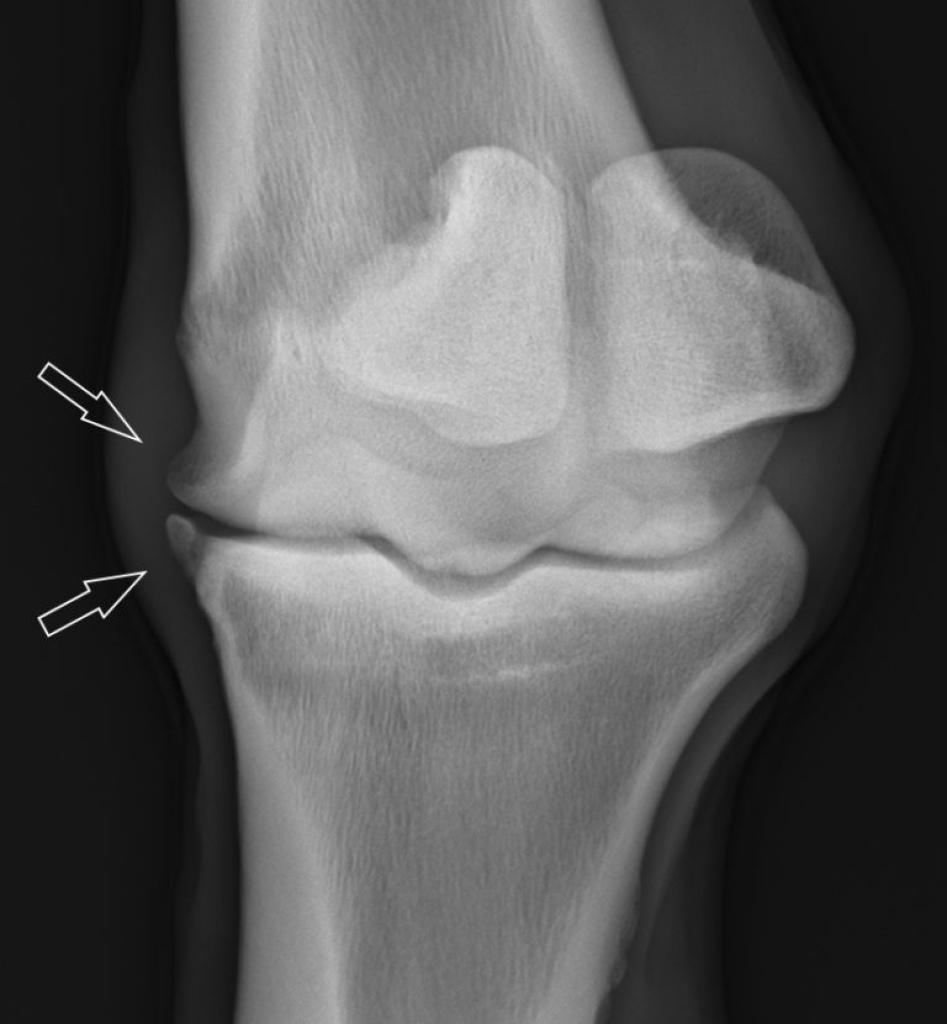

artrose paard

Het gebruik van stamcellen in gewrichten bij artrose

Er zijn verschillende onderzoeken gedaan naar het effect van stamcel therapie bij artrose. Vooral uit studies in de humane geneeskunde blijkt dat stamcel therapie leidt tot vermindering van de ontstekingsreactie in het gewricht en daardoor leidt tot vermindering van de pijn. Ook zijn er een aantal publicaties waaruit blijkt dat de kwaliteit van het kraakbeen licht verbeterde maar de hoeveelheid en dikte van het kraakbeen niet duidelijk toenam. Stamcel therapie is dus zeker ook effectief bij artrose maar heeft meestal maar een tijdelijk effect. Dit komt onder andere omdat stamcellen minder goed functioneren in een ontstoken milieu.

Verder kunnen bij lokale kraakbeen beschadigingen in een gewricht stamcellen een groot verschil maken in het herstel. Ook bij meniscusblessures en artrose in de knie bij paarden is  wetenschappelijk aangetoond dat stamcellen een positieve invloed hebben op het herstel. De kwaliteit van het littekenweefsel in de meniscus en de kwaliteit van het kraakbeen was beter. Dit vertaalde zich in een grotere kans op herstel en terugkeer in de sport.